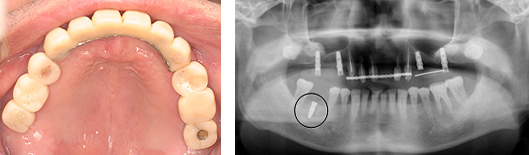

丸印が昨日インプラントを埋入したところです。

上顎は現在仮歯をいれ、咬み合わせの調整をしています。